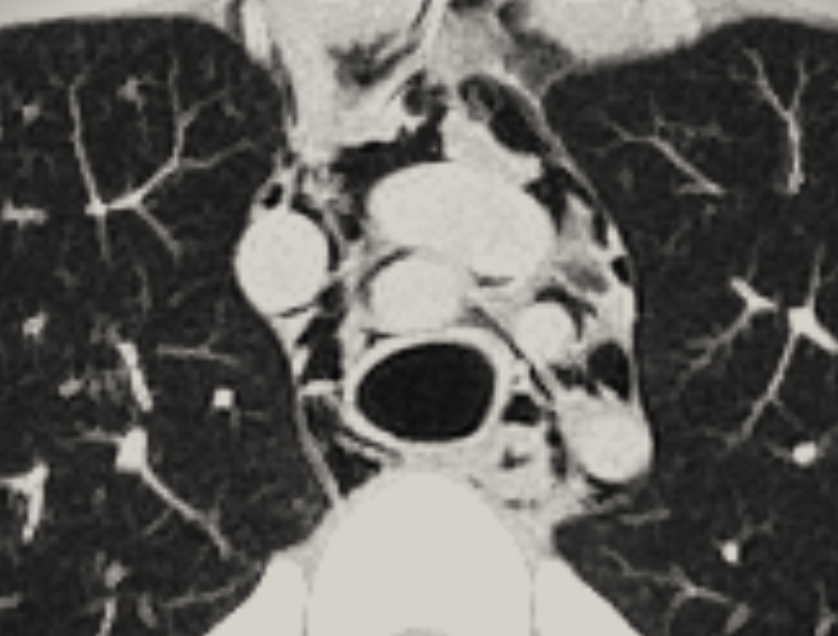

#PLEURAL_PEARLS_WA 34 Pneumomediastinum is rare; associated with smoking/inhaled drugs; trauma; iatrogenic procedures. Chest pain, dyspnea, dysphagia often settle with conservative care. Easy to miss on CXR; CT best for diagnosis/see extent. TSANZ AABIP

#PLEURAL_PEARLS_WA 34

Pneumomediastinum is rare; associated with smoking/inhaled drugs; trauma; iatrogenic procedures. Chest pain, dyspnea, dysphagia often settle with conservative care. Easy to miss on CXR; CT best for diagnosis/see extent.